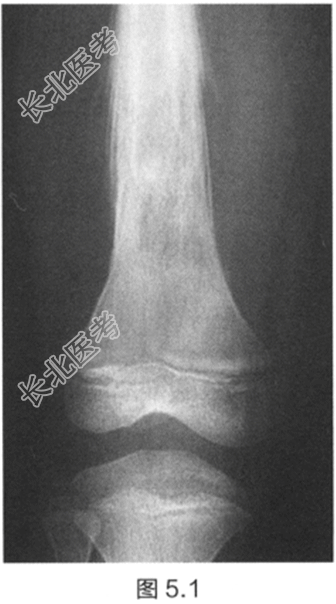

- [材料题] 一名14岁男孩,全科医师发现他股骨中段有明显肿胀。患者还抱怨近几周内自觉疲劳和间歇性发热,导致无法进行少年足球训练。检查:触诊大腿中部,发现一压痛性肿块。推移肿块无活动性。腿部未发现神经或血管受累。初步检查显示白细胞(WBC)、红细胞沉降率(ESR)升高和贫血。股骨X线片如图5.1所示。

- 简答题1、诊断是什么?

- 简答题2、描述X线片所见。

- 简答题3、如何处理?预后如何?